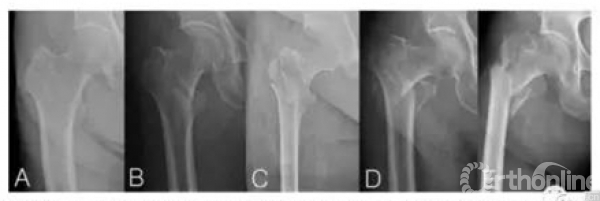

Fig.2.The Jensen modification of Evans classification.(A)type1-two part.Undisplaced,(B)type2-two part.displaced,(C)type3-three part.loss of posterolateral support,(D)type4-three part.loss of medial support and,(E)type5-four part.